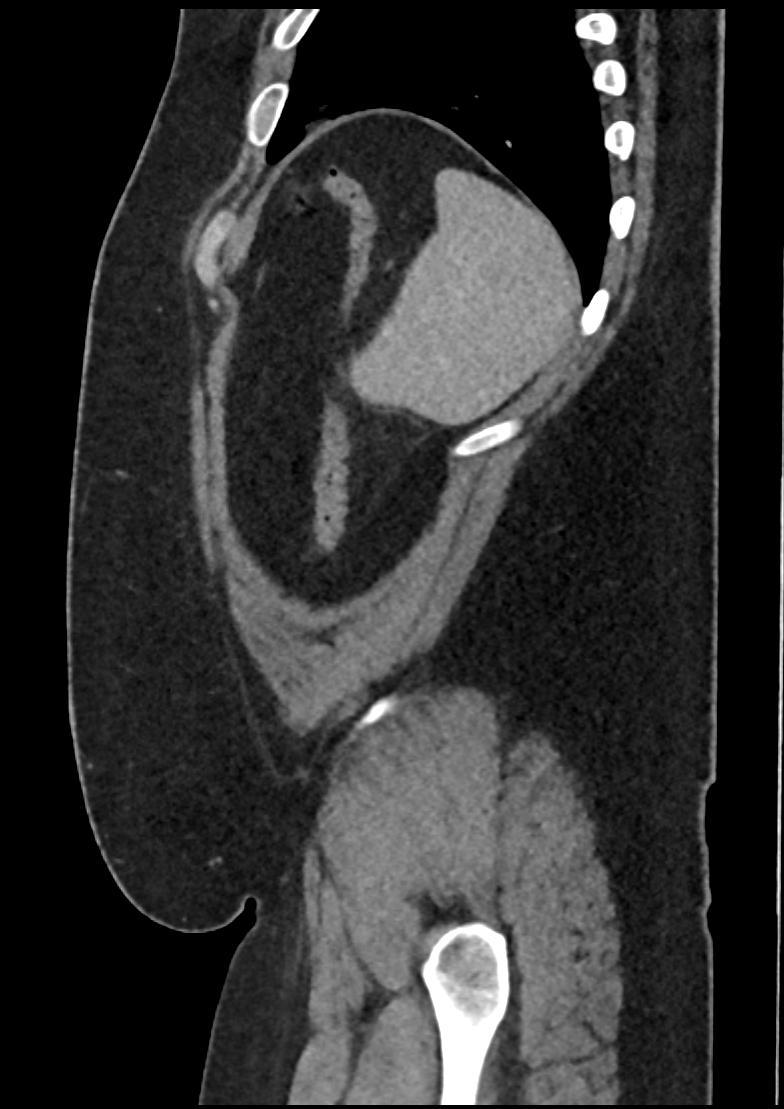

Patient: Padmakumar A. , *1988-04-24, PID: 3000069741773230809

Study Description: CT ABDOMEN

Image Series: Abdomen Sag 3mm [4]